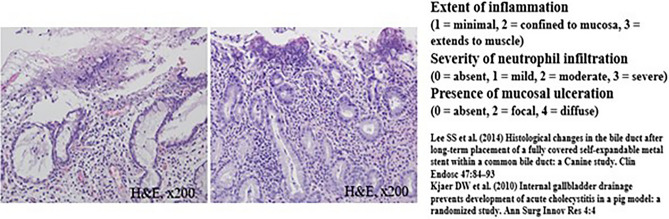

The common bile duct (CBD) diameter was 2.5 ± 0.5 mm in macroscopic findings. The biliary stricture length measured after harvesting of experimental animals was 36 mm ± 0.5 mm in macroscopic findings. Using H&E-stained tissue sections, the degree of histological damage was compared by examining the depth of inflammation, the degree of deposition of neutrophils, the presence of mucosal ulceration, and the overall score (Figs. 4, 5 and Tables 1, 2). The total histological score indicating histological damage of plastic stents was observed to be higher for the 3-month point than that for the 1-month point total score, median (range) of 1-month pigs vs. 3-month pigs: 6 (6–8) vs. 6.5 (6–8), although their difference was not statistically significant (p = 0.057) (Fig. 4 and Table 1). However, in the animal group in which the plastic stents were mounted for 5 months, the total score was observed to be significantly higher than those mounted for less time (total score, median (range) of 3-month pigs vs. 5-month pigs: 6.5 (6–8) vs. 9 (9–9), p = 0.029) (Fig. 5 and Table 2). The degree of tissue damage was compared using immunofluorescent staining (Fig. 6). From the top to the bottom, photomicrographs of H&E, Masson Trichrome staining, and immunofluorescence staining using CK 19 are shown. H&E staining revealed that the deposition degree of neutrophils of the tissue in the contact area of the plastic stents (Fig. 6). When the same area was observed after Masson Trichrome staining, extensive fibrosis of the tissue in the contact area was observed. At the bottom of Fig. 6, the immunofluorescent staining was performed using CK 19 for histologic evaluation.

In this study, we performed H&E staining, Masson Trichrome staining, and immunofluorescence staining (CK 19) to achieve an objective histopathological evaluation. Furthermore, the veterinarian pathologist in the animal laboratory evaluated and calculated the histological score based on the histological scoring system shown in Supplementary Table 1 commonly used in previous studies13–15. Histological damage caused by plastic stents was found to be higher when the follow-up time was longer. Interestingly, the total histologic score did not show any significant differences between different time points less than 3 months after inserting biliary plastic stents. However, at 5 months after stent insertion, a statistically significant difference in histological score was observed compared to that at shorter follow-up. Considering our results and cost effectiveness of the animal study, 1-month point after RFA seems to be the best timing for testing the new devices in the BBS in vivo swine models. Therefore, in clinical practice, it is recommended to remove the plastic stent between 3 and 6 months, which is the average patency period in previous studies16–18 to avoid histological damage.

Histopathological examination and evaluation

Pigs were euthanized at 1 month, 3 months, and 5 months after biliary plastic stents were inserted. Histopathological examination was then performed. After the liver, biliary tract, gallbladder, and duodenum were removed from experimental animals, a large amount of KCl (Potassium Chloride) was injected to induce euthanasia. From the extracted liver, biliary tract, gallbladder, duodenum, and AoV were dissected to the proximal end of the plastic stent located in the right and left intrahepatic bile duct. After the dissection, an incision was made in the longitudinal direction to confirm the proximal intrahepatic bile duct and distal biliary duct stenosis. The bile duct tissue was incised from the intrahepatic bile duct into which different plastic stents had been inserted and cut into sections, followed by H&E staining and Masson Trichrome staining. Histopathological examination was performed to reinforce the histological scoring method of previous studies. Scoring was performed in a blinded method using H&E-stained tissue sections. All sections were classified according to the extent of inflammation (1) (1, minimal; 2, confined to mucosa; and 3, extended to muscle with neutrophil infiltration). The severity of neutrophil infiltration was scored (2) as 0 for Absent, 1 for Mild, 2 for Moderate, and 3 for Severe. The presence of mucosal ulceration (3) was scored as 0 for Absent, 2 for Local, and 4 for Diffuse (Supplementary Table 1)13–15. Based on the histological scoring system shown in Supplementary Table 1, the histological score was calculated by a veterinarian pathologist in the animal laboratory of Samsung Life Sciences Research Institute.